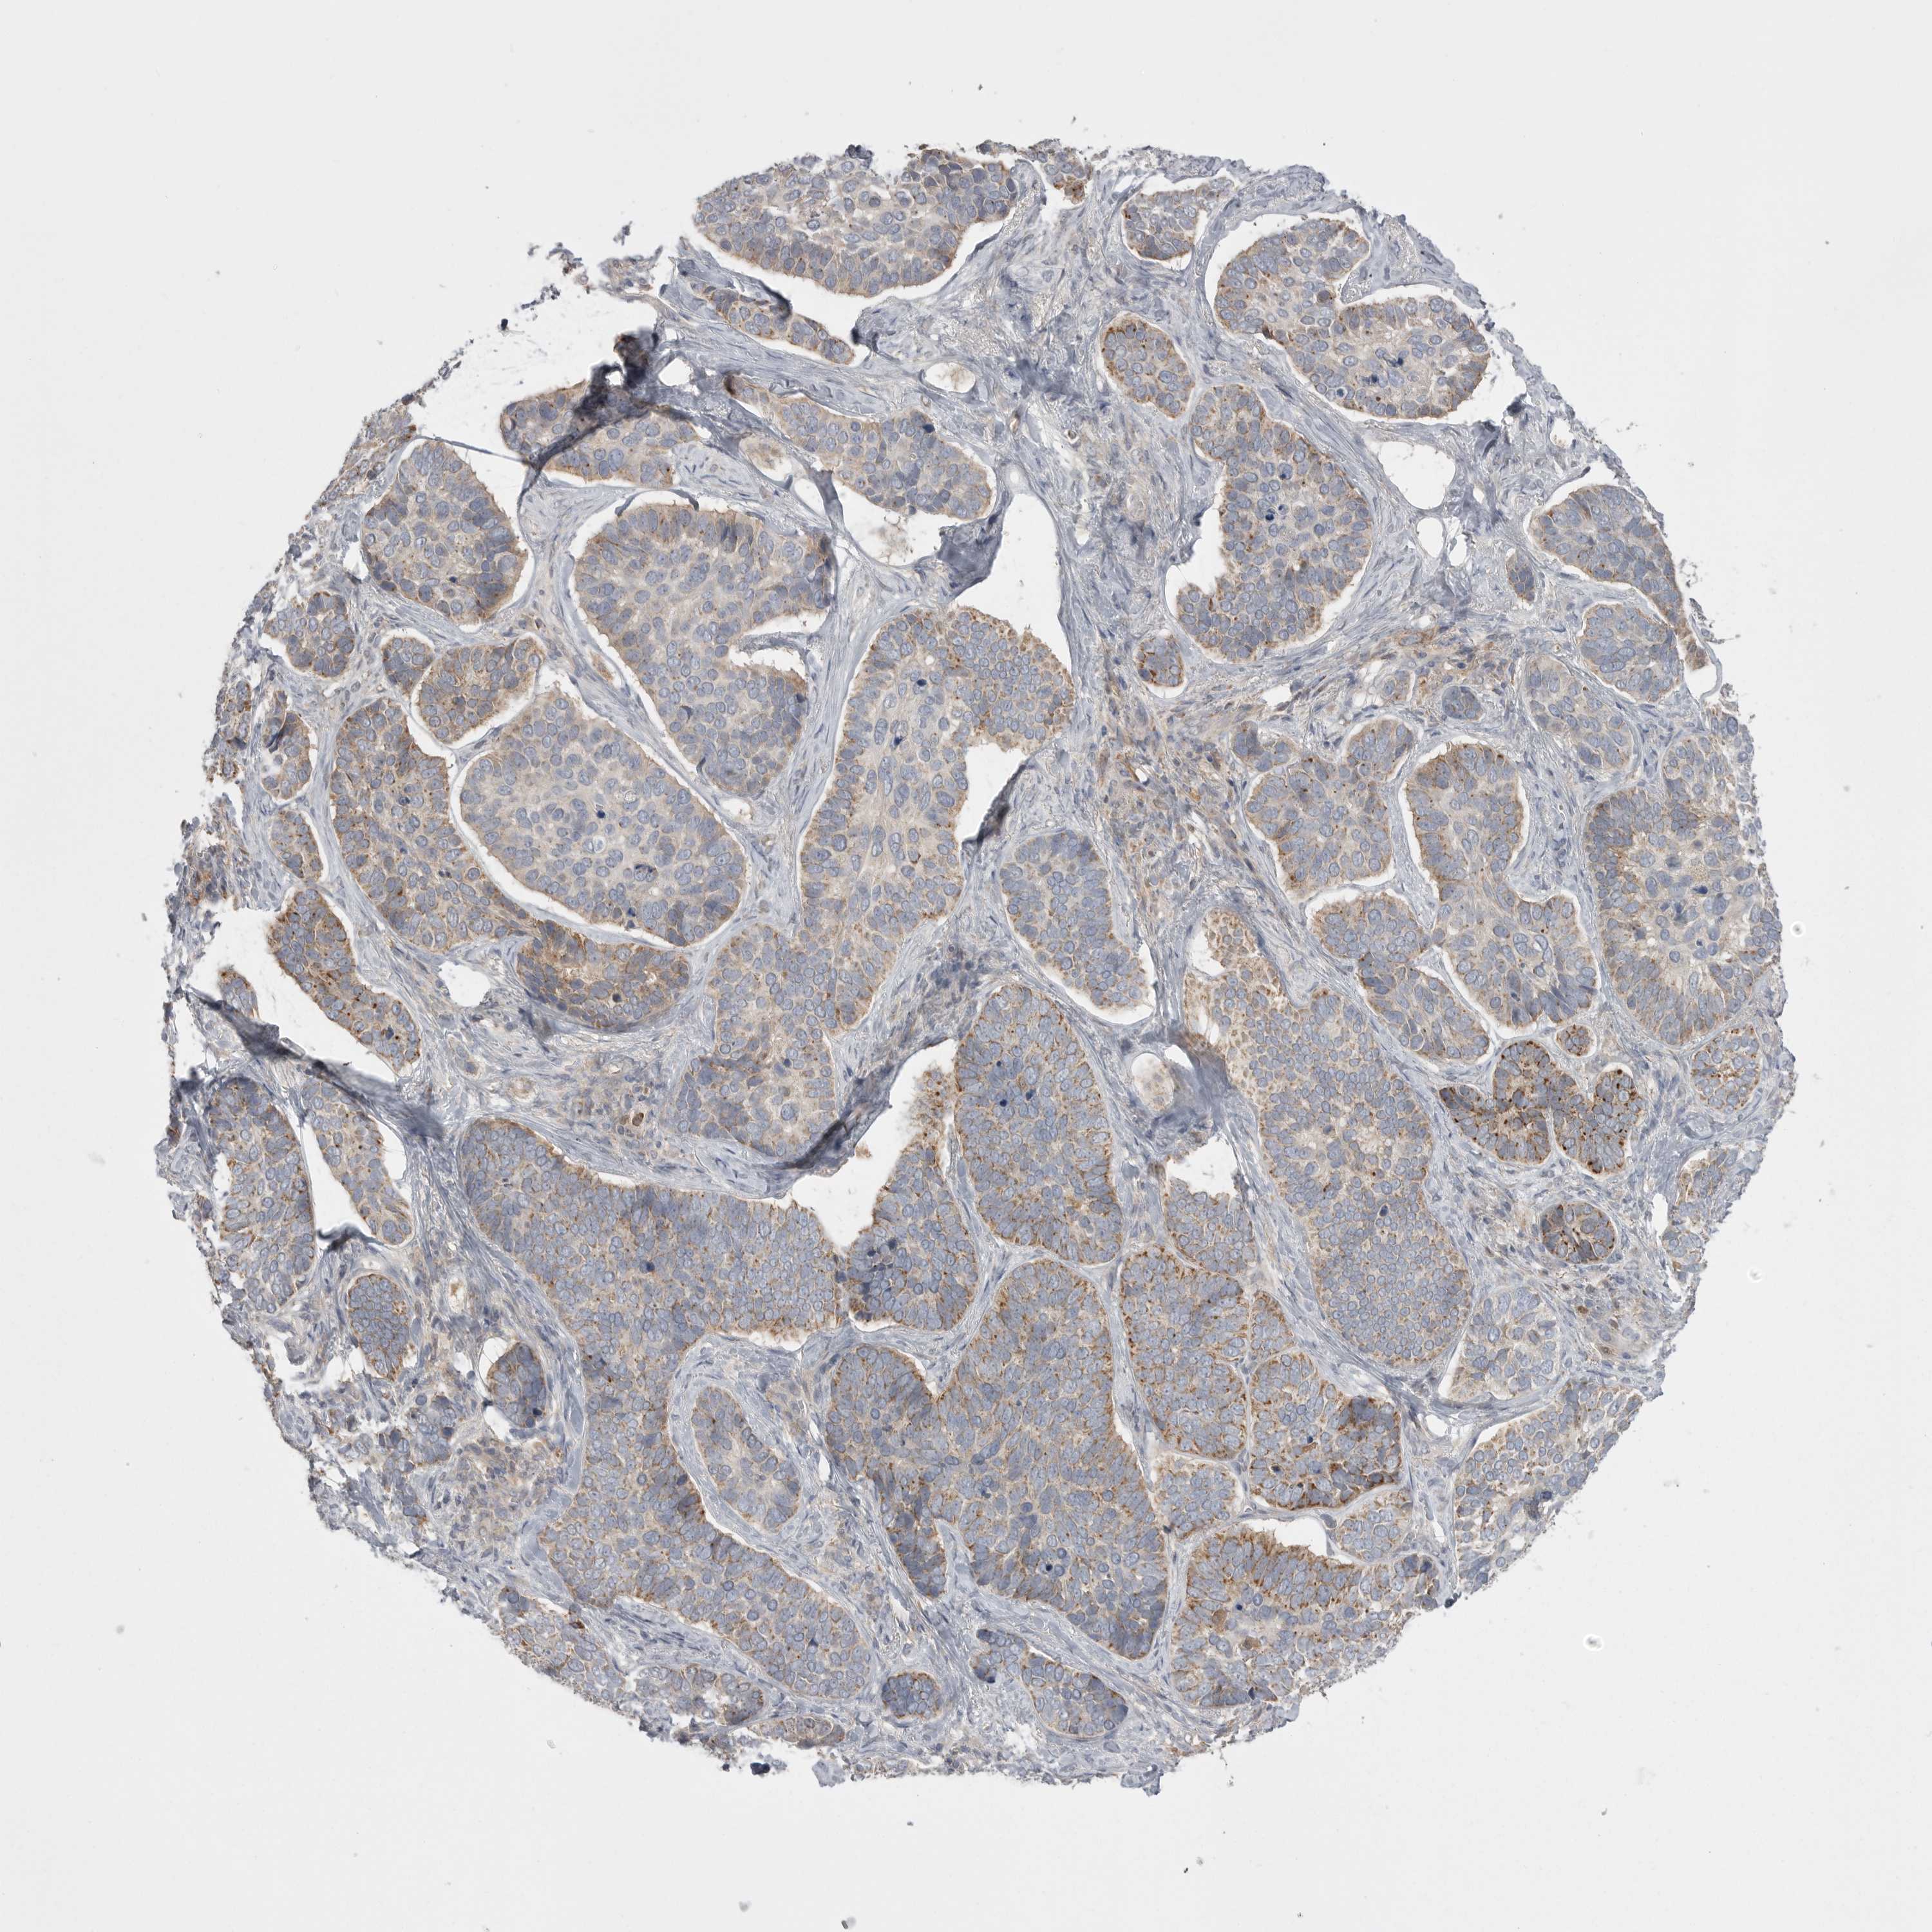

SKIN CANCER - Protein expressioni

A mouse-over function shows sample information and annotation data. Click on an image to view it in a full screen mode. Samples can be filtered based on level of antibody staining by selecting one or several of the following categories: high, medium, low and not detected. The assay and annotation is described here.

Antibody stainingi

Antibody staining in the annotated cell types in the current human tissue is reported as not detected, low, medium, or high, based on conventional immunohistochemistry profiling in selected tissues. This score is based on the combination of the staining intensity and fraction of stained cells.

Each image is clickable and will lead to virtual microscopy that enables deeper exploration of all samples and also displays staining intensity scores, fraction scores and subcellular localization as well as patient and tissue information for each sample.

Antibody HPA026538

Basal cell carcinoma